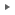

● 上顎乳歯犬歯が抜けなかったことによる不整咬合

乳歯犬歯が抜けなかったことにより、永久歯犬歯が前方に移動し(より鼻先の方向)下顎の犬歯により永久歯犬歯が外側に持ち上げられてしまっています。

緑:上顎永久歯犬歯。適正な場所よりも前方かつ外側にある

青:上顎乳歯犬歯。本来は抜けているべきであるが、抜けていないために、永久歯犬歯(緑)を異常な場所に圧迫している。

赤:下顎永久歯犬歯。正常な位置よりも内側かつ前方にずれている。また上顎の永久歯犬歯(緑)を下から押し上げている。